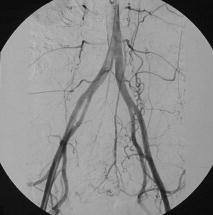

Abb. 2

Abb. 4

Abb. 6